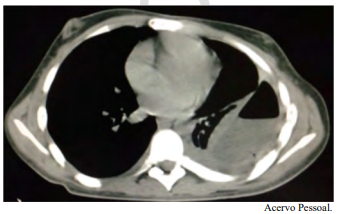

Um paciente do sexo masculino, jovem de 21 anos de idade, com diagnóstico prévio de esquizofrenia, foi internado para investigação de alteração na tomografia de tórax, conforme a imagem a seguir. A clínica apresentada era perda de peso, febre vespertina, tosse e um episódio de hemoptise. É familiar contactante de paciente com tuberculose ativa.

Com base nesse caso clínico e nos conhecimentos médicos correlatos, julgue o item a seguir.

O mais provável fator de risco para a condição que o paciente apresenta é exposição ao asbesto e ao tabaco.